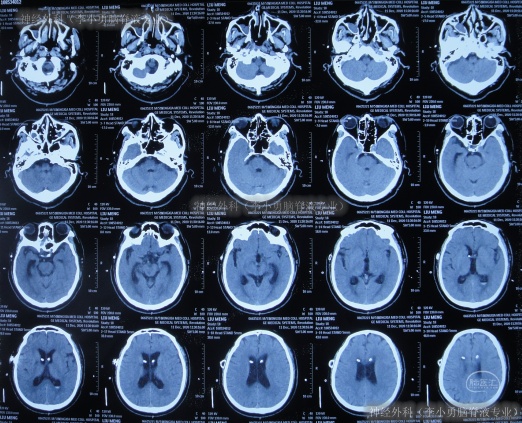

住院1周左右时间,期间曾3次查头颅CT(图-2)示脑室稍有扩张,但头晕症状慢慢消失,行走不稳缓解,认为“病情变好”出院。

图-2:3次查头颅CT